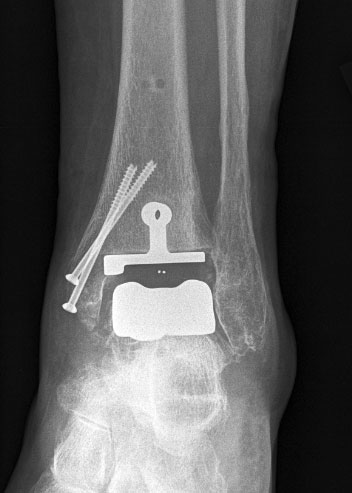

Osteosynthese eines intraoperativ frakturierten medialen Malleolus mit perkutanen Schrauben.

Abbildung 19

1. intraoperative Innenknöchelfraktur:

Mögliche Ursachen können eine zu weit medial plazierte Tibiakomponente oder eine zu weit mediale, nicht nach lateral konvergierende Sägerichtung im Rahmen der ventrodorsalen distalen Tibiaresektion sein (Abb. 19).